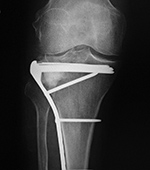

63 year-old woman with lateral tibial plateau fracture treated by a lateral buttress plate and Norian bone graft substitute.